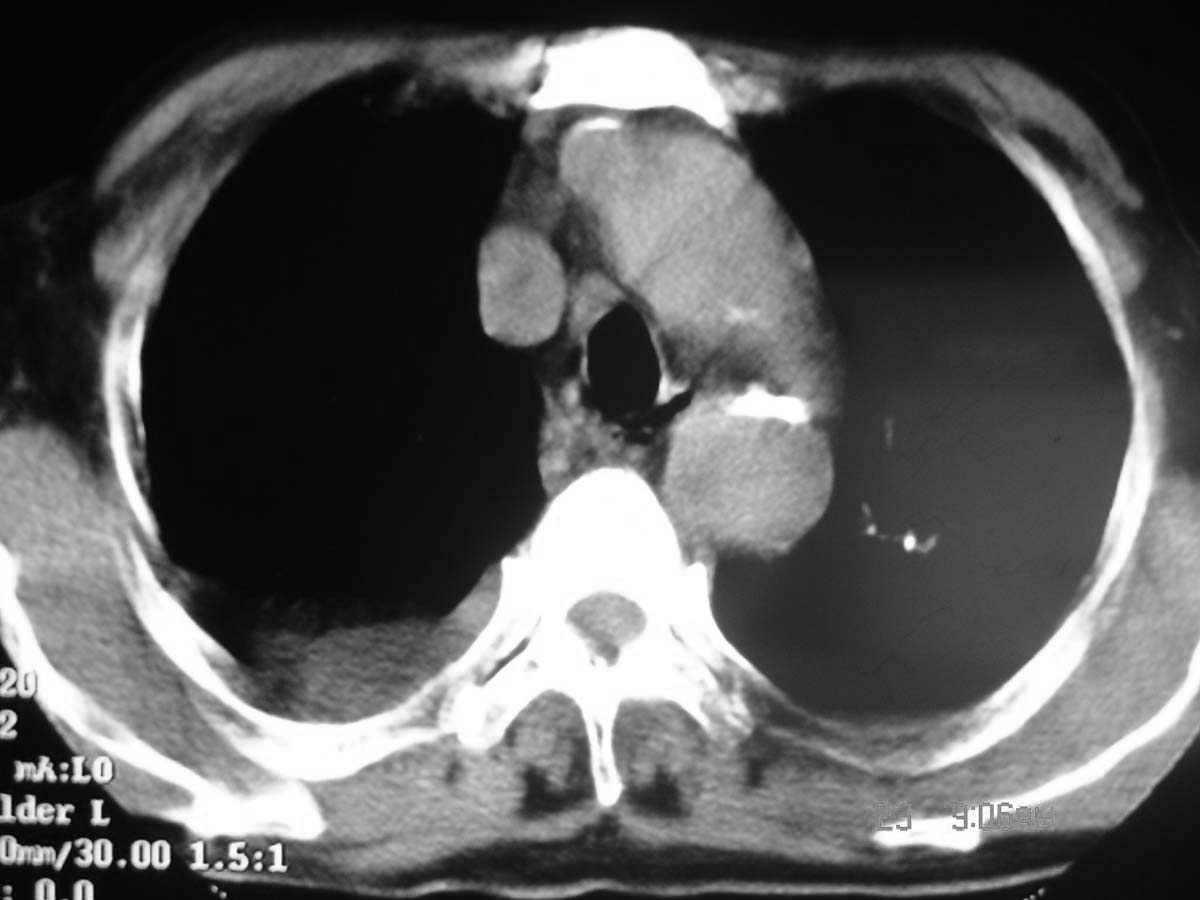

以下是引用守望可可西里在2006-11-23 14:33:00的发言:[br][br] 糖尿病病人很容易继发结核,病人又有双侧胸膜增厚、粘连、胸腔积液以及双上肺的斑片状、条索状影结核病灶影,以一元论考虑,右下肺病变首先考虑干酪性肺炎,可以正规抗炎治疗后复查,排除一般的肺炎。